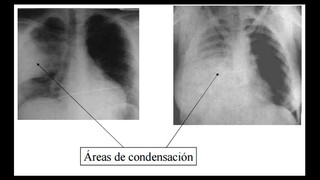

Signos de importancia del tórax

Generalidades del tórax y pulmón